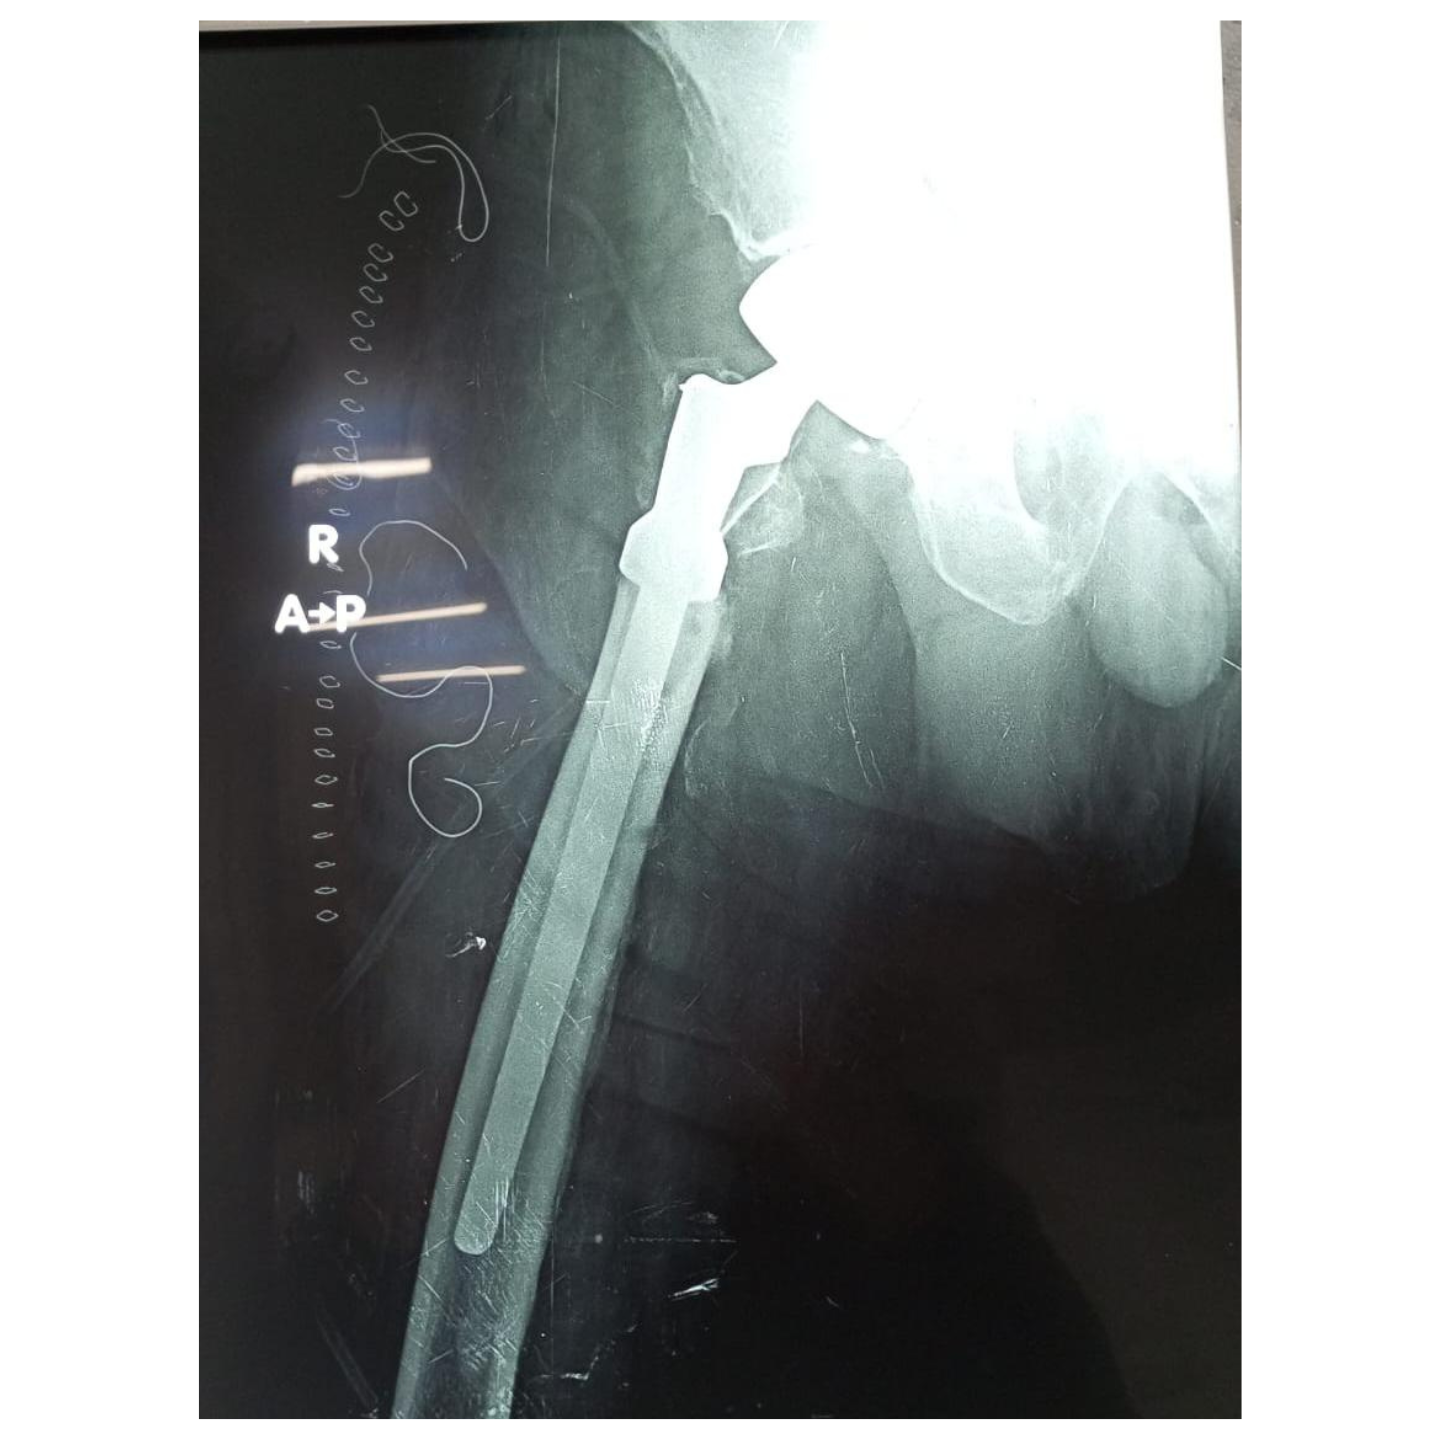

Revision Total hip replacement surgery

Bilateral total hip replacement surgery